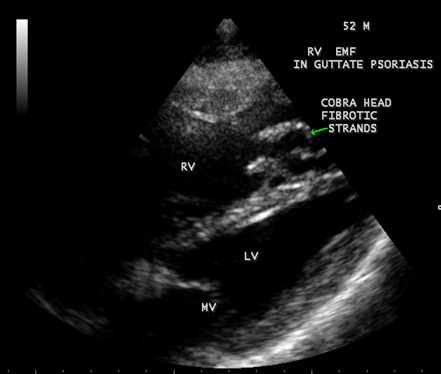

Transthoracic echocardiography revealed strong fibrous strands appearing as ‘finger like projections’ or ‘cobra-head’ appearance in the right ventricular apex due to fibrosis of muscular trabeculae, suggesting right ventricular endomyocardial fibrosis as shown in Figures 3 to 7.

Figure 3: Subcostal view showing the ‘finger like’ projections of fibrous strands in the RV (right ventricular) apex suggesting Right ventricular endomyocardial fibrosis in a 52-year old male with psoriasis.

Figure 4: Tilted apical view showing the ‘cobra-head’ appearance of fibrous strands suggesting right ventricular endomyocardial fibrosis in a 52-year old male with Psoriasis.